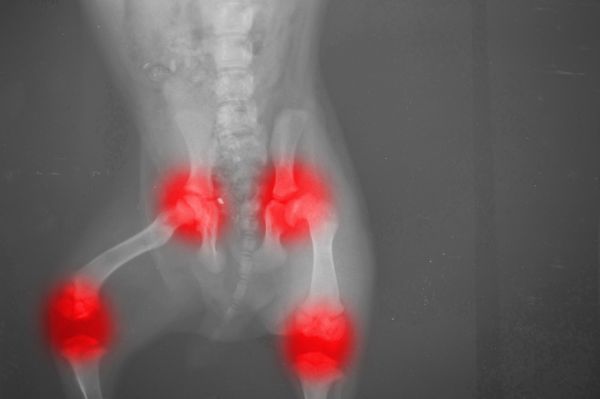

Arthritis in dogs is a common condition, affecting one in five adult dogs. It is a major cause of chronic pain in older dogs and can result in permanent joint damage. The most commonly affected joints in dogs are the hips, knees, shoulders and elbows.

Arthritis in cats was considered an uncommon condition in the past, but more recently this has been disproved. A study in 2011 showed that 61% of cats over 6 years old had at least one joint evidencing arthritic change, and a 2002 study showed that up to 90% of cats over 12 years showed signs of the disease. In cats, the most commonly affected joints are the shoulders, elbows, hips and spine.

As the signs of arthritis in cats and dogs can be very subtle, it often goes undiagnosed. If arthritis is suspected, the vet will perform a physical examination, take X-rays, perform blood tests and use other diagnostic tests to investigate the cause of the disease.

- A radiograph or x-ray, performed under general anaesthetic, can confirm arthritis. In some cases, a contrast dye will be injected into the joint prior to the x-ray.